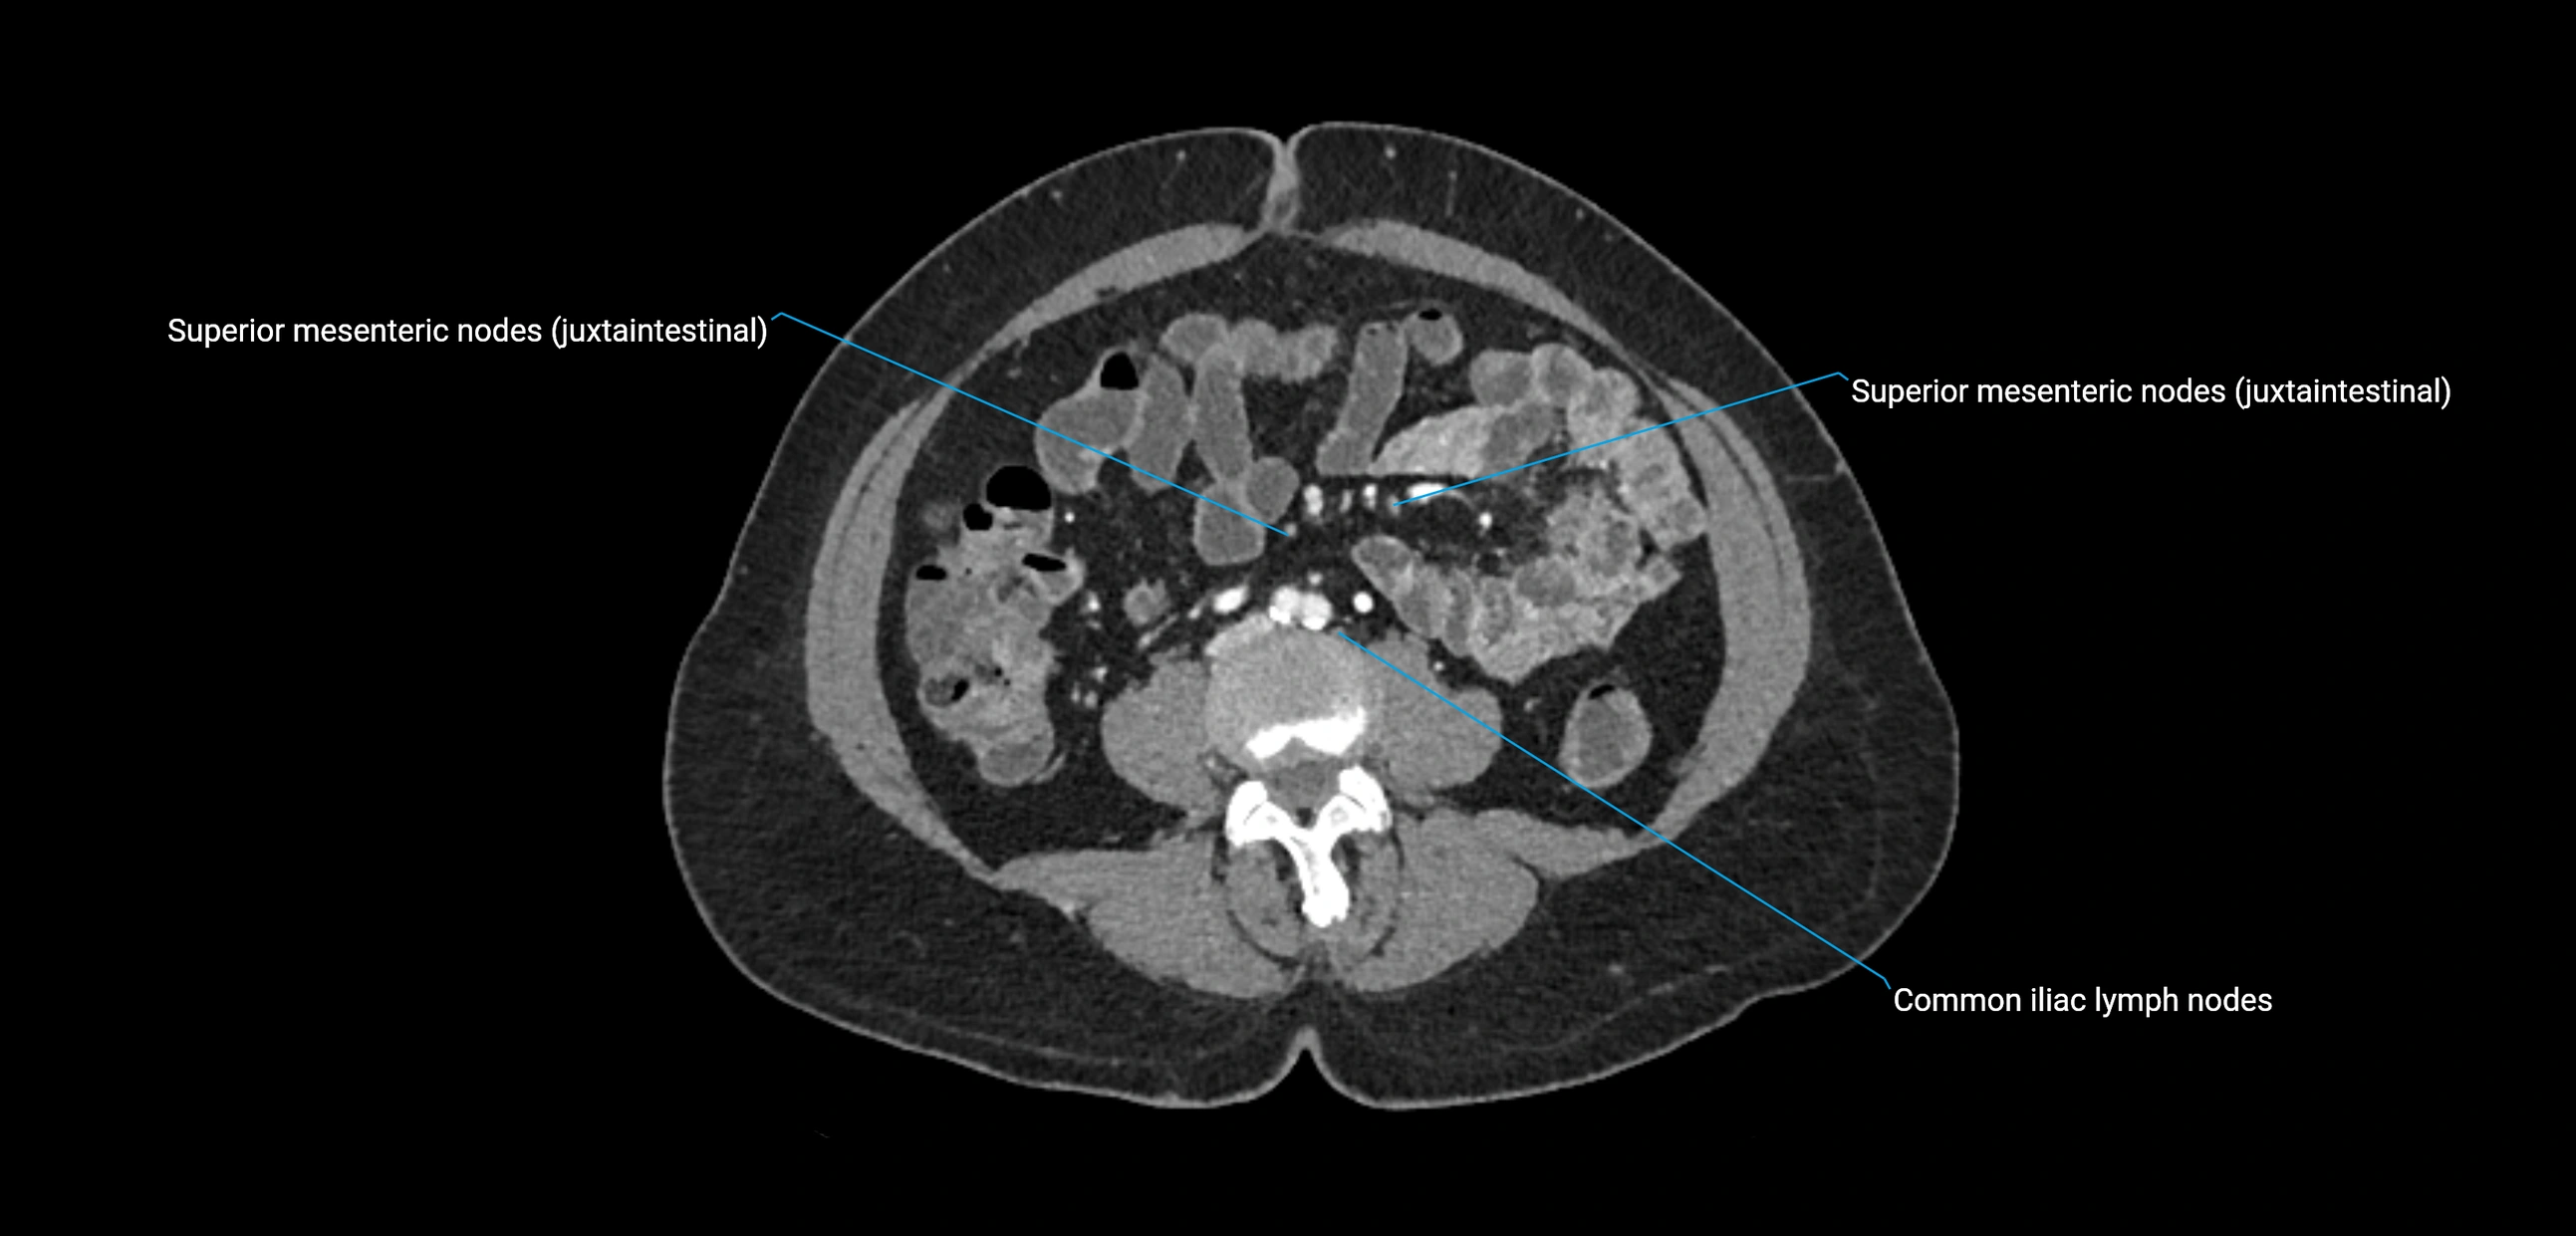

CT Appearance

CT Pre-Contrast:

• Nodes appear as soft-tissue density nodules adjacent to the aorta and IVC

• Calcification may be seen in chronic infections (e.g., tuberculosis)

CT Post-Contrast:

• Normal nodes enhance homogeneously

• Malignant nodes may show heterogeneous enhancement, central necrosis, or conglomerate formation

• Size >1 cm short axis is suspicious, though morphology and distribution are equally important

CT image

image